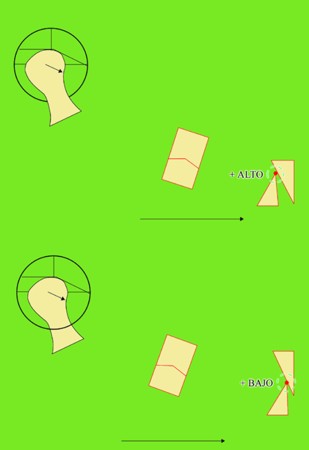

Primera Parte RESUMEN: La alta complejidad inherente a los procedimientos de Rehabilitación Oral, obligan al profesional que la ejerce a basarse en parámetros multidisciplinarios, a veces lo suficientemente intrincados que hacen imposible la práctica de la misma, sin la presencia en su mente de una clara concepción de la Oclusión. The extreme complexity of Oral Procedures, make it imperative for the working professional to rest on multidisciplinary parameters, sometimes so complex that make impossible its practice without the presence of a clear idea of Oclusion. DESARROLLO Suele ser sumamente árido el abordaje de un tema como Oclusión, desde la perspectiva de nuestro diario trabajo ,con todo el strees que este conlleva, con toda la lucha que significan citas, honorarios, diferentes personalidades de los pacientes, inquietudes de los mismos, etc. «LA MEJOR OCLUSIÓN ES LA QUE TIENE LA MEJOR DESOCLUSIÓN» Básicamente, podemos como desde hace ya muchos años se viene haciendo; clasificarlos en: A)Determinantes Posteriores (fijos) Más contemporáneamente, en: I-Mecanismos Primarios: A.T.M. GUIA ANTERIOR INCLINACIÓN DEL PLANO OCLUSAL CURVA SAGITAL DE SPEE FORMA DE LA ARCADA III-Mecanismos Elementales CRESTAS TRIANGULARES INTERNAS Analicemos cada uno de ellos: Es evidente, que la reproducción de las características de la A.T.M., en nuestro aliado fundamental, el Articulador; es imprescindible. Partiendo de la premisa de obtener una OCLUSIÓN MUTUAMENTE PROTEGIDA, para luego arribar al concepto de OCLUSIÓN MUTUAMENTE COMPARTIDA, concepto este que desarrollaremos durante el transcurso de las distintas entregas, analizaremos cada uno de los FACTORES DETERMINANTES DE LA OCLUSIÓN. El primero de ellos, por ser fijo e invariable, solo diremos que: son sus INCLINACIONES PLANARES, o sea : A-INCLINACIÓN DE LA TRAYECTORIA CONDILEA C-BENNET INMEDIATO articuladores totalmente ajustables) D-DISTANCIA INTERCONDILAR. En cuanto a la GUÍA ANTERIOR, mecanismo primario y por supuesto anterior, provee al cuerpo mandibular; del camino a recorrer durante las excursiones protrusivas y lateralidades, a través del vínculo entre las piezas dentarias anteriores, superiores e inferiores. En un corte sagital, podemos observar la relación entre estos donde vemos que se vinculan sin entrar en un contacto franco, sino más bien en una relación de vencindad muy intima a la que llamamos: PUNTO DE ACOPLAMIENTO. Otros factores fundamentales de la GUÍA ANTERIOR son : A-ALTURA FUNCIONAL B-PUNTO DE ACOPLAMIENTO En cuanto a los SURCOS, sabemos que durante una Transtrusión, las cúspides fundamentales generan surcos sobre las piezas que antagonizan. Dichos surcos proveen de una vía de escape a las cúspides antagonistas para evitar colisiones, con las indeseables fuerzas laterales cuya gravedad ya conocemos. MECANISMOS SECUNDARIOS La CURVA FRONTAL DE WILSON, se observa invertida a nivel de los caninos y de los primeros premolares. El PLANO OCLUSAL, en realidad no es ningún plano, sino la sumatoria de muchos MICROPLANOS, los cuales individualmente pueden constituir factores presentes en la OCLUSIÓN, pero auténticos problemas para la DISCLUSIÓN. La CURVA SAGITAL DE SPEE, denominada originariamente de BALKWIL-SPEE, fue concebida como una curva. El cuarto factor SECUNDARIO: el ANCHO DE LA ARCADA, es evidente que variando los ejes de rotación , alrededor de las diferentes distancias ;cambiará la dirección de los escapes (surcos), de los elementos que en el se muevan (cúspides). MECANISMOS ELEMENTALES Los CUATRO NIVELES DE OCLUSIÓN y las CRESTAS TRIANGULARES INTERNAS, constituyen de por si, la herramienta ejecutora de las funciones gnáticas. A- ELEVACIONES 1-Puntas Cuspídeas B-DEPRESIONES 1-Fosas SURCOS DE DESARROLLO De las CRESTAS TRIANGULARES INTERNAS, acentuamos su importancia en ellas dado que son las efectoras finales de la molienda, y su triangularidad debe tener su base partiendo del surco y su vértice terminando en la Punta Cuspídea, condición importante para evitar colisiones durante la transtrusión (movimiento de lateralidad ). EFECTOS DE LA VARIABILIDAD DE LOS FACTORES DETERMINANTES DE LA OCLUSÍON Cada uno de los determinantes influye aumentando o disminuyendo tanto la DESOCLUSIÓN como la ALTURA CUSPÍDEA INCLINACIÓN DE LA TRAYECTORIA SAGITAL INCLINACIÓN DEL PLANO OCLUSAL RADIO DE CURVATURA DE LA ÁNGULO DE LA TRAYECTORIA ALTURA DEL PUNTO DE LATERO SURTRUSIÓN / MOV. DE BENNET INMEDIATO CURVA FRONTAL DE WILSON SURCOS BIBLIOGRAFÍA Dibujos y esquemas tomados del libro: Oclusión Orgánica…un camino hacia la Rehabilitación Oral. 1)William Mc Horris,B.S.,D.D.S. Oclusión. Con especial énfasis sobre :El rol funcional y parafuncional de los dientes anteriores. 2)Von Spee , Craff(Anatomista alemán, describió la curva de compensación de la articulación de molares y premolares).CURVA DE SPEE 1.89 3)Stuart,D.»Some aspects of the inervation teeth.»Procedings of Royal Society of Medicine.20:1675,19274)Muhleman,H. y Savdir,S»Tooth movility-its causes and significance»Journal of Periodontology ,36:153,Marzo ,Abril,1965. 4)Muhleman,H. Y Savdir,S»Toothmovility its causes and significance» Journal of Periodontology,36:153,marzo,abril,1965. 5-Oclusión y Diagnóstico en Rehabilitación Oral. 6-Anatomia Odontológica. -A contribution to the study of the movementes of the mandible. 8-Celenza F.W, Nadeskin J.F.,Oclusión.Situación actual. 9-D´Amico 10-Dawson P.E. 11-Huffman -Regenos. 12-Hobo S.-Takayama H.A. 13-Lucia V.O 14-Mc Horris. 15-Mc Horris. 13-Posselt U. 16-Stuart C. 17-Vartan Veshnilian

Ahora bien, como; la variabilidad de cada uno de estos factores influye sobre nuestros patrones oclusales, es una cuestión a desmenuzar:

ACOPLAMIENTO

A mayor altura, mayor altura cuspídea, mayor desoclusión.